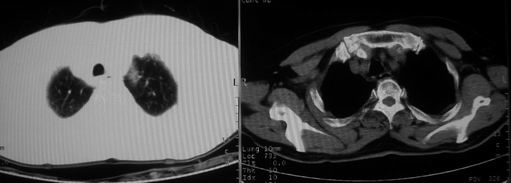

10月9日片:

ct左肺下叶大片状高密度影,病变密度不均,界限不清,左侧胸腔积液,治疗后复查临床症状好转而影像学表现病变有发展,还是首先考虑感染性病变,复查时间短附合感染性病变的病理改变。

两肺炎症感染(以左肺下叶为著),双侧少量胸腔积液;建议继续抗炎治疗。